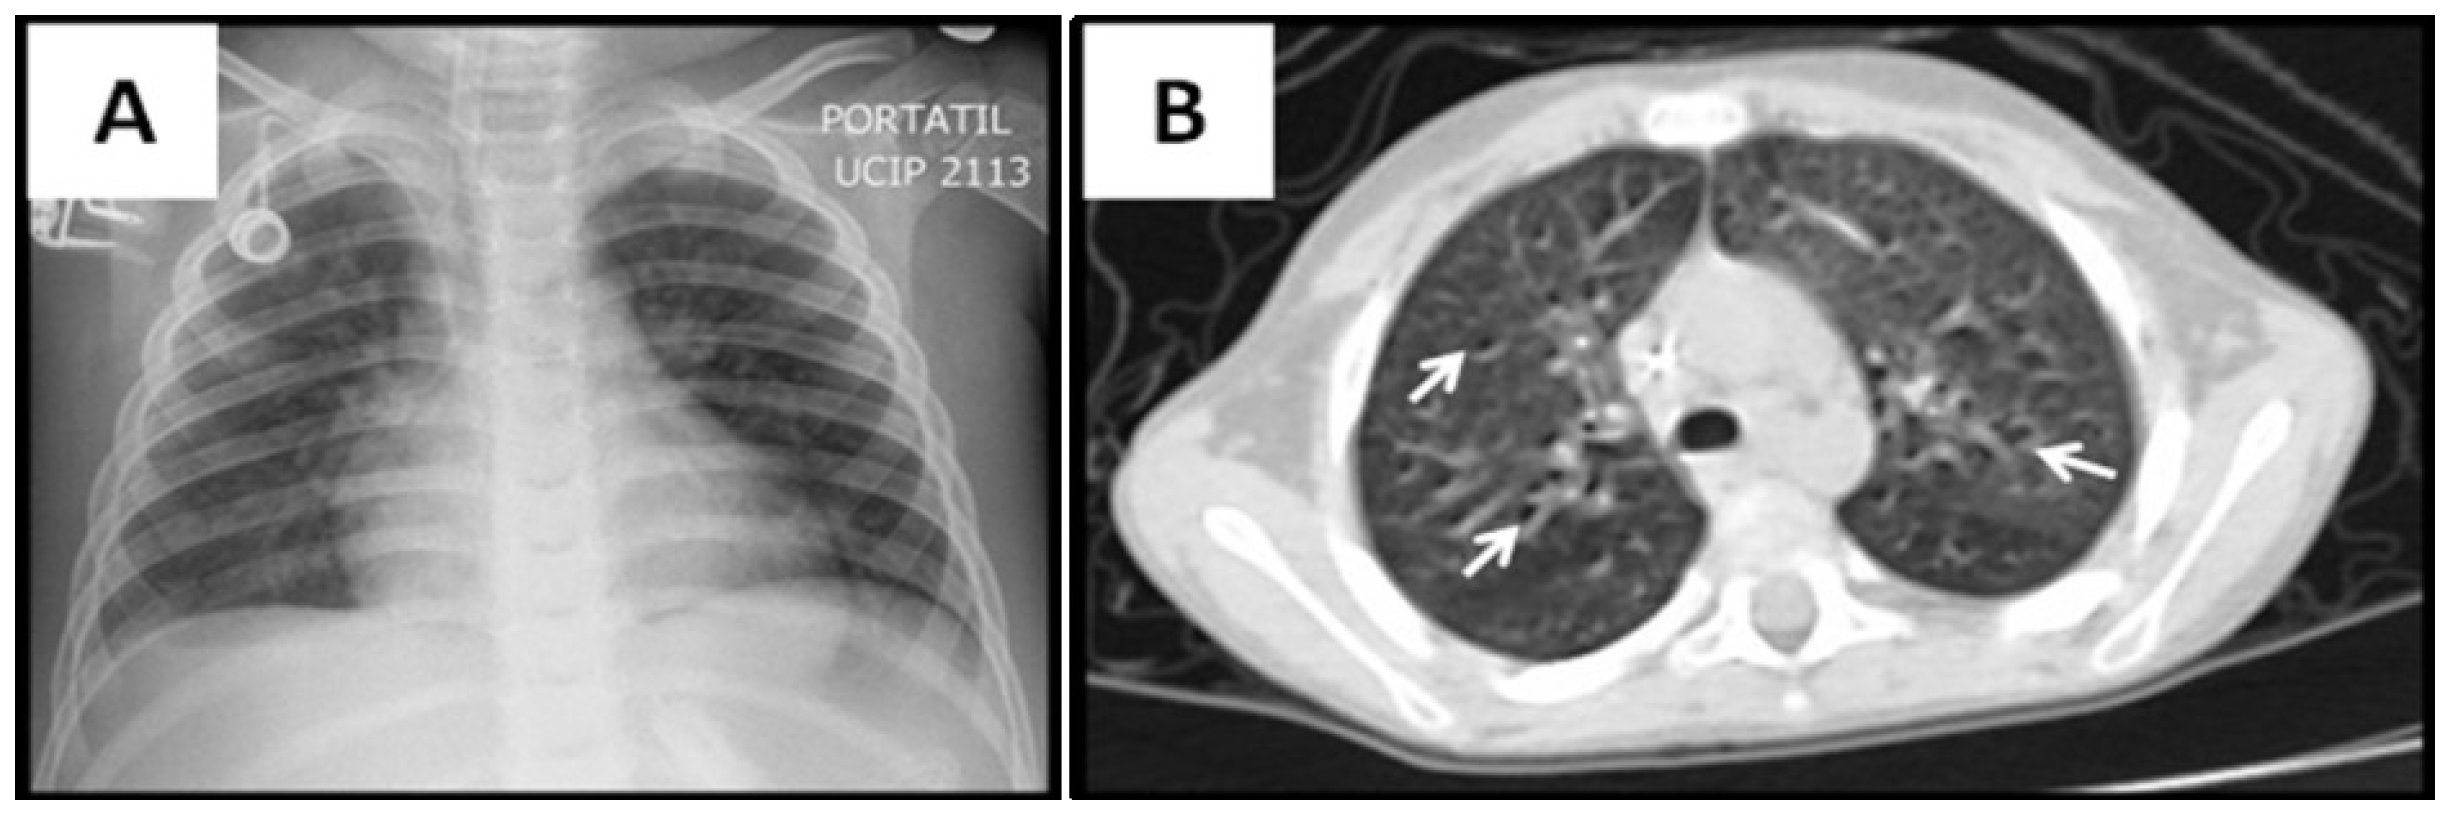

3.2. Radiological Findings in CMV Lung Infection

| Radiological variables | |

| Abnormal lung images, n (%) | 15 (100) |

| Ground-glass opacity, n (%) | 12 (80) |

| Consolidation, n (%) | 12 (80) |

| Atelectasis, n (%) | 6 (40) |

| Air trapping, n (%) | 5 (33) |

| Nodular pattern, n (%) | 3 (20) |

| Reticular pattern, n (%) | 1 (6) |

| Tree-in-bud pattern, n (%) | 1 (6) |